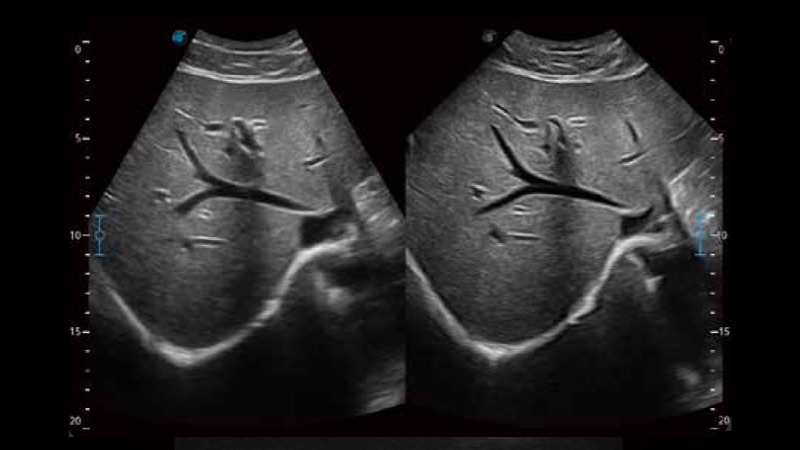

開立醫(yī)療通過不斷的技術(shù)創(chuàng)新,為大眾的生命健康提供持續(xù)關(guān)愛。P12 Plus采用全新一代超聲成像平臺,新平臺旨在將真實還原組織解剖結(jié)構(gòu)作為首要目標(biāo)。平臺采用全新集成化硬件模塊,搭載新一代芯片,系統(tǒng)性能得到大幅提升,為您的診斷提供了豐富的臨床信息。優(yōu)異的圖像表現(xiàn),豐富的探頭配置,全面的應(yīng)用功能,為您日常診斷提供了可靠的助手。